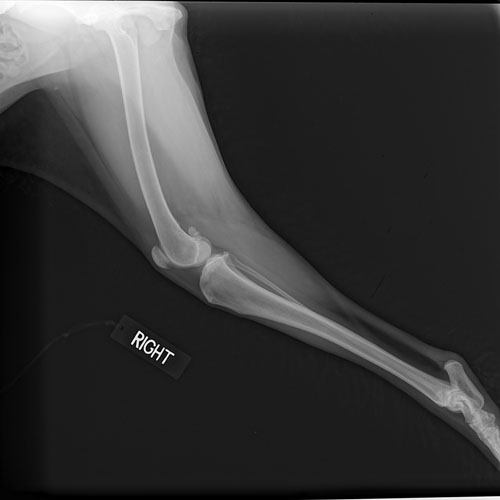

New Albany Animal Clinic uses x-ray as a diagnostic tool as well as guidance for surgery. If your pet comes in for an emergency visit, he or she may receive an x-ray as a starting point to identify the problem. Radiography can help identify fractures, locate foreign bodies, discover masses or tumors, measure organ size, diagnose pneumonia as well as pregnancy. All x-rays contain some component of radiation, however, rest assured that our staff will never put your pet’s health at risk with overexposure.